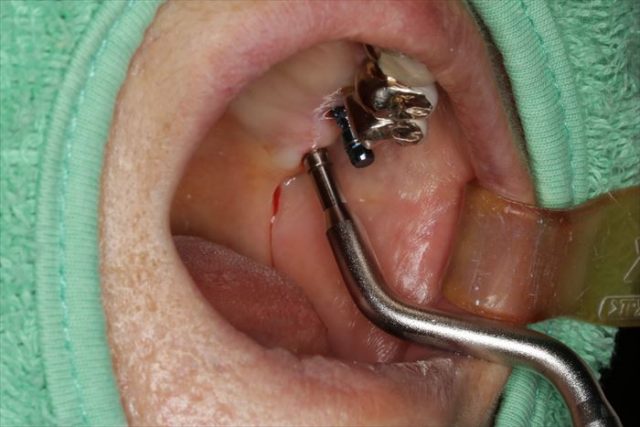

いつものようにサージカルステントを製作してインプラントオペに臨みます。

オステオトームを用いて上顎洞をさらに数ミリ拳上して

フラップレス(粘膜の剥離を行わない)でインプラント窩(インプラントを稙立する穴)を形成します。

頬側面観です。

青いパーツはインプラント埋入用の挿入ジグです。